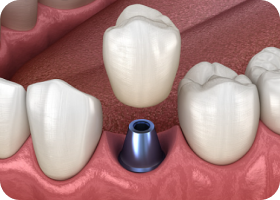

바른선택 뼈이식 STAGE 03

임플란트 치근 식립

이식된 뼈가 충분히 자리잡으면,

그 위에 임플란트 치근을 식립하여

단단하게 고정될 수 있도록 합니다.

바른선택 뼈이식 STAGE 04

보철물 제작 및 장착

임플란트가 잇몸뼈에 고정된 후,

개인의 구강 구조에 맞춘 정밀한 보철물을

식립하여 편안한 저작 기능을 회복합니다.